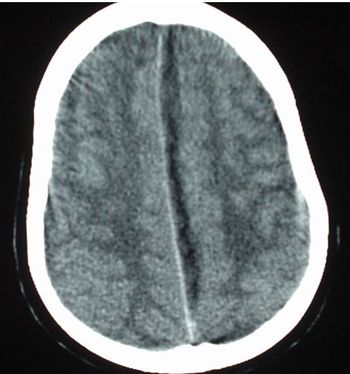

The patient has had 10 episodes of bleeding in the past 24 hours. Can you find clues to the underlying problem in the history and on the CT scan?